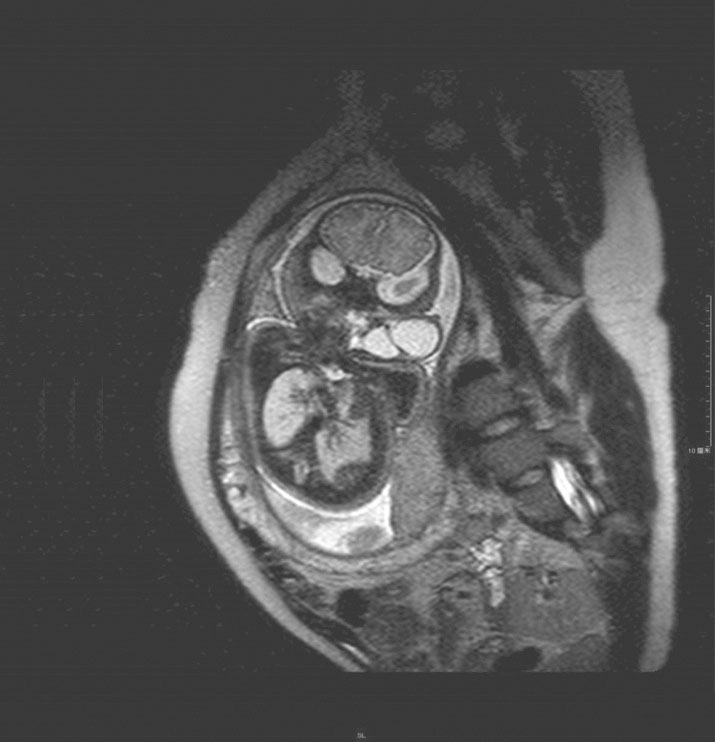

(2)颈部巨大肿物:主要为畸胎瘤、淋巴管瘤、血管瘤、食管重复畸形、咽后壁肿块、颈部巨大鳃源性囊肿、甲状腺肿、神经母细胞瘤等。此类疾病患者在生后可因颈部巨大肿物压迫气道、无法通气而死亡,由于EXIT的应用,在胎儿胎盘循环下进行气管插管或气管切开建立气道通气后、断脐,再处理肿物(如切除瘤体),已大大提高了患者的存活率(图6-14、图6-15)。

图6-14 胎儿颈部巨大淋巴管瘤MRI